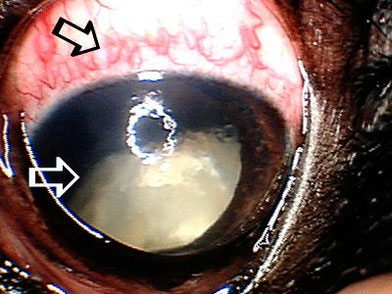

I cani affetti da HC (cataratta ereditaria) sviluppano cataratte ad entrambi gli occhi in giovane età. La condizione non è congenita per cui gli occhi si presentano normali alla nascita ma la cataratta appare a poche settimane o mesi di età del cucciolo, fino alla progressione totale con conseguente cecità intorno ai 2/ 3 anni di età.

Il PHPV è una patologia oculare congenita causata dal mantenimento di elementi della vascolarizzazione fetale alla lente. Il risultato è la condizione in quantità variabili di placca fibrovascolare sulla capsula posteriore del cristallino e la possibile cataratta corticale posteriore. Questo è spesso accompagnato da sanguinamento nella parte posteriore dell'occhio. Il PHPV è ereditario nello Staffordshire Bull Terrier, anche se la modalità precisa di ereditarietà non è nota.